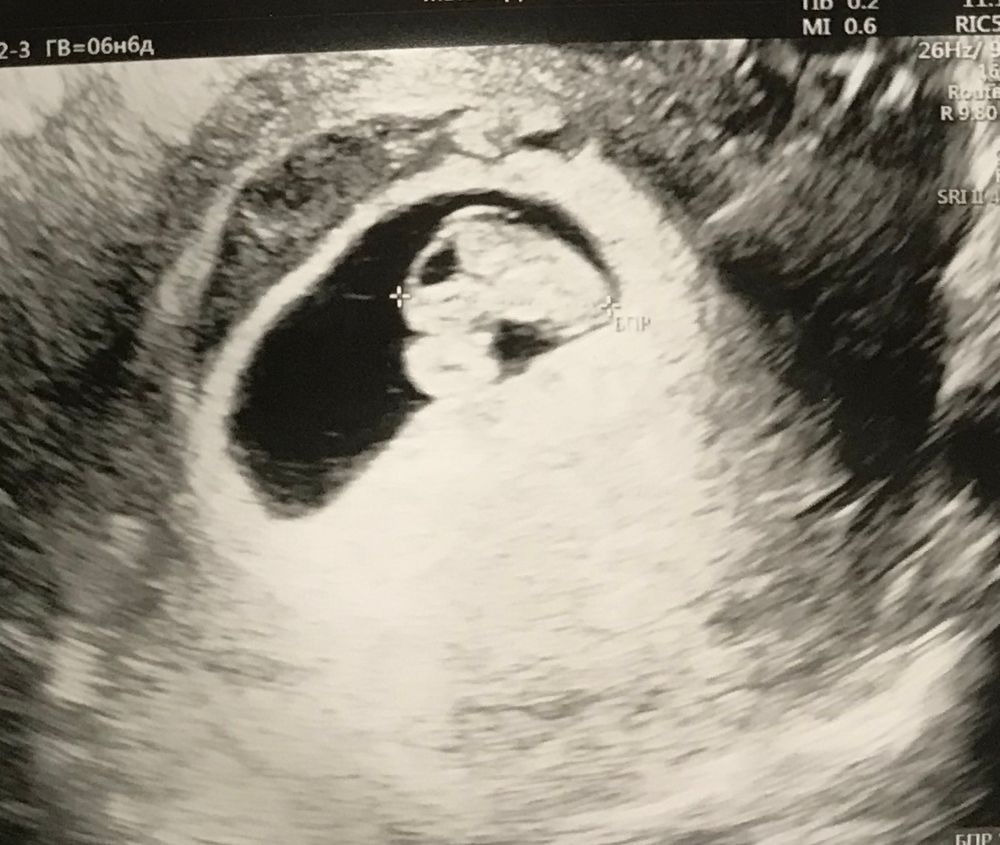

Дарья Тарасенко, моё узи на 7 недель Изображение

23.11.2022